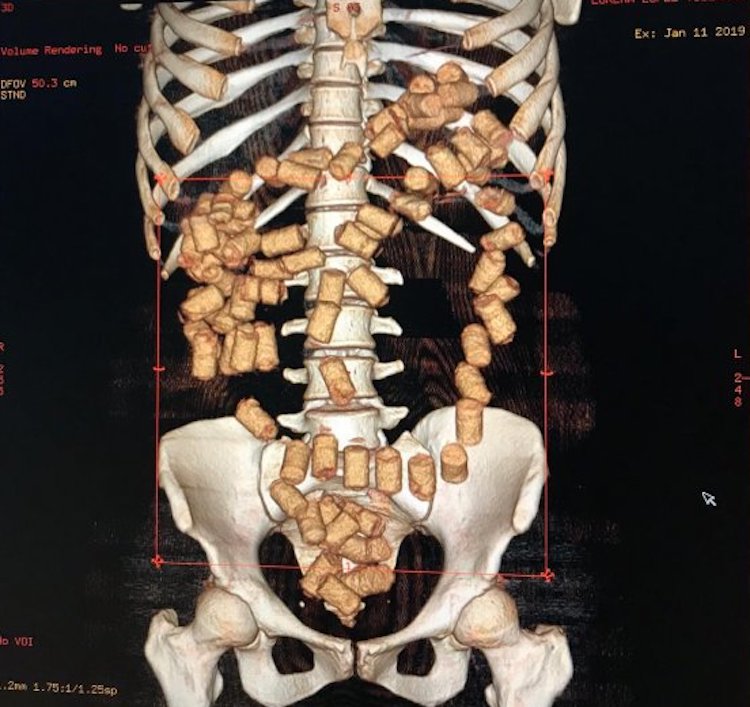

Foz de Iguazú: Eine 24-jährige Paraguayerin wollte vom Flughafen der Stadt über São Paulo nach Valencia, Spanien fliegen. Sie hatte 87 Kokainkapseln im Körper sowie 300 Gramm der Droge in ihrer Vagina.

Die 87 Kapseln aus ihrem Verdauungstrakt sowie die 300 g aus ihrer Vagina könnten etwa 1 kg erreichen, was in Europa zwischen 80.000 – 90.000 Euro Wert ist. Die Frau wurde nach dem Anfangsverdacht ins Stadtkrankenhaus gebracht, wo man die Drogen mit einem 3D-Scanner fand. Die Füllung ihrer Vagina überraschte niemand. Sie wurde verhaftet.

“Bodypacking“, das Schmuggeln von Suchtgift im Körper, wird den Kurieren von Drogenorganisationen in Südamerika in “Schulen“ beigebracht. Auf Flughäfen werden im Schnitt alle jede Woche ein Bodypacker festgenommen.

Fingerlinge sind gefüllte Kondome, die gut verpackt und verklebt werden. Sie sollen eine mehrstündige Reise im Flugzeug von Südamerika nach Europa überstehen. Platzen sie, ist das für den Bodypacker tödlich.